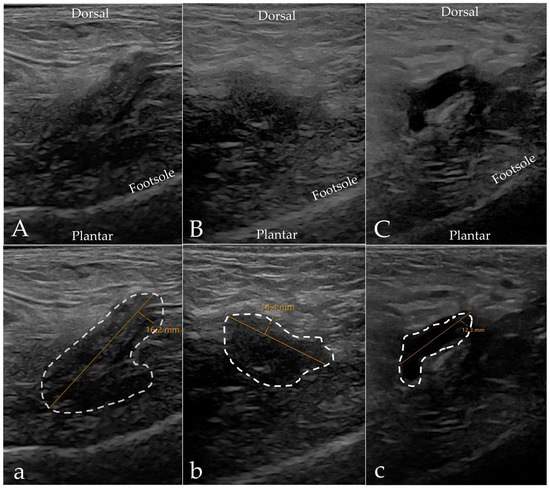

3.2. Imaging Results